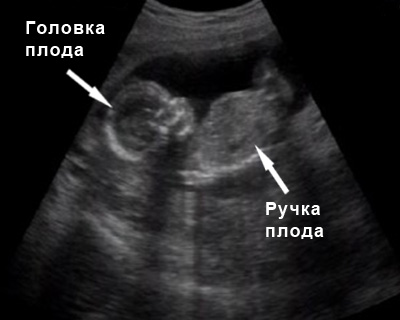

Например, в 11-14 недель УЗИ позволяет установить размеры т. н. шейно-воротникового пространства.

До 15-ой недели УЗИ дает возможность с высокой степенью точности определить срок по размерам плода. Позже этот показатель малоинформативен, так как на размеры (рост) уже влияют генетические (наследственные) факторы.

Расшифровка результатов УЗИ плода BPD – бипариетальный диаметр, HC – окружность головы будущего малыша, CRL – длина малыша, определяемая расстоянием от темени и до крестца, FL – длина кости бедренной.